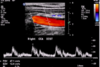

In which direction is blood flowing in the vascular duplesx US (DUS) image shown below?

to the left

ðf = doppler shift